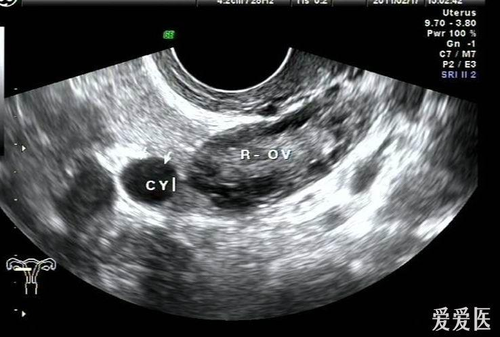

2. 因为其并没有明显的临床不适症状,大多是进行其他疾病超声检查时发现了部位有小囊肿,对此不要过度紧张,通常输卵管系膜囊肿未引起症状时,大多为生理性或退化性的改变所发生的囊肿,并不需要通过手术进行治疗。